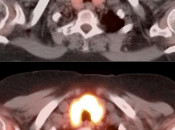

Case 4 (Image 2)

Axial images confirm the uptake to represent a hypodense left lobe thyroid nodule, containing a punctate calcification. As ≈ 30% of hypermetabolic thyroid nodules represent a primary thyroid cancer, such nodules require ultrasound evaluation (biopsy is usually necessary). In this case, biopsy revealed a primary thyroid cancer.

Case 7 (Image 2)

Axial images also demonstrate this diffuse intense uptake. The CT image suggests a slightly enlarged and nodular morphology of the gland.

Case 7 (Image 3)

Given the rather bulbous appearance of the thyroid isthmus, the intensity of the MIP image was manually decreased. This decreased intensity reveals a hypermetabolic nodule masked by the diffuse intense uptake. Biopsy revealed a primary thyroid cancer.